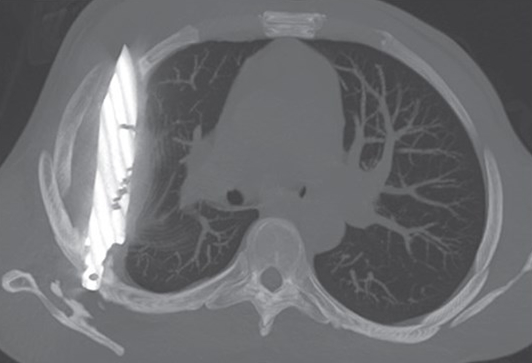

Incredibly, a chest radiograph found the cause of his current ailment – a large knife blade lodged in the mid-thorax.

Doctors could see the knife had entered through the right scapula, and had managed to dodge any major organs.

An image showing a large metallic (knife) foreign body removed from the middle lobe of the right lung. (Jam Press/Journal of Surgical Case Reports)